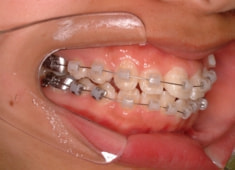

治療開始から5ヶ月後